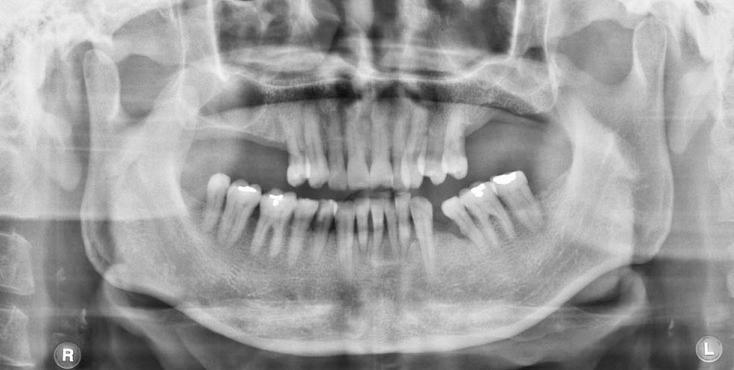

全景X线片上颈动脉钙化诊断的观察者间一致性。

Interobserver agreement on the diagnosis of carotid artery calcifications on panoramic radiographs.

This study was performed to investigate the interobserver agreement on the detection of carotid artery calcifications on panoramic radiographs.

This study consisted of panoramic radiographs acquired from 634 male patients of the age of 50 years or older. Having excluded carotids of no diagnostic quality, 1008 carotids from the panoramic radiographs of the patients were interpreted by two oral and maxillofacial radiologists independently for the presence of carotid artery calcifications. Statistical analysis was used to calculate the interobserver agreement.

Interobserver agreement was obtained for 932 carotids (92.4%). Inconsistent interpretation of 76 carotids (7.5%) between the two observers was found. Cohen's kappa value was 0.688 (p<0.001).

The probability of a match between the two observers was substantially high.

本研究旨在调查全景X线片上颈动脉钙化检测的观察者间一致性。

本研究纳入了634例年龄在50岁及以上男性患者的全景X线片。排除诊断质量不佳的颈动脉后,两名口腔颌面放射科医生对患者全景X线片上的1008条颈动脉独立解读,以确定是否存在颈动脉钙化。采用统计分析计算观察者间一致性。

932条颈动脉(92.4%)达成了观察者间一致性。发现两名观察者之间对76条颈动脉(7.5%)的解读不一致。科恩kappa值为0.688(p<0.001)。

两名观察者之间匹配的概率相当高。